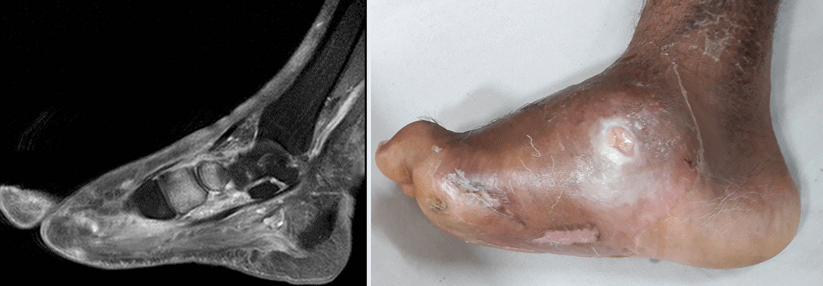

Die chemotherapieinduzierte periphere Neuropathie (CIPN) ist eine häufig dosislimitierende Folge von Taxanen. Ein Team aus Heidelberg prüfte jetzt randomisiert die Wirksamkeit von Kälte und Kompression zur Prävention der CIPN im Halbseitenversuch.

An der POLAR-Studie nahmen 122 Brustkrebspatientinnen teil, die als adjuvante/neoadjuvante Therapie vier Zyklen Epirubicin + Cyclophosphamid gefolgt von zwölf Zyklen Paclitaxel oder nab-Paclitaxel mit oder ohne Trastuzumab oder Carboplatin erhalten sollten. Wie Dr. Laura L. Michel vom Nationalen Centrum für Tumorerkrankungen (NCT) und der Universitätsklinik Heidelberg berichtete, erhielten sie 1:1 randomisiert an der dominanten Hand als präventive Maßnahme entweder eine Kühlung oder eine Kompression, während die andere Hand als Kontrolle diente.

Zum Kühlen wurde ein mit ­Elasto-Gel gefrorener Handschuh verwendet, die Kompression erfolgte mit zwei übereinander gezogenen OP-Handschuhen, die…